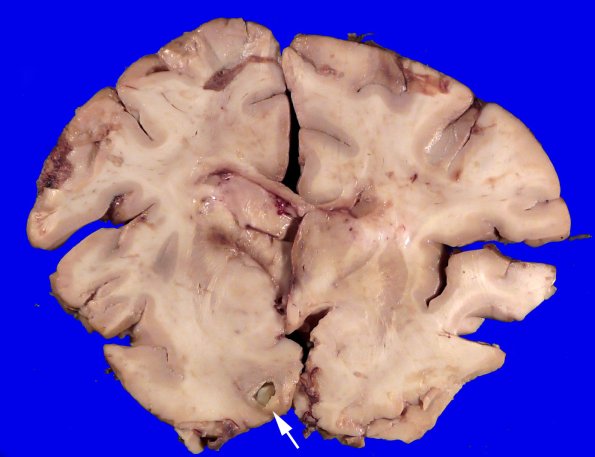

The origin of this abscess shows clear location at the gray/white junction.